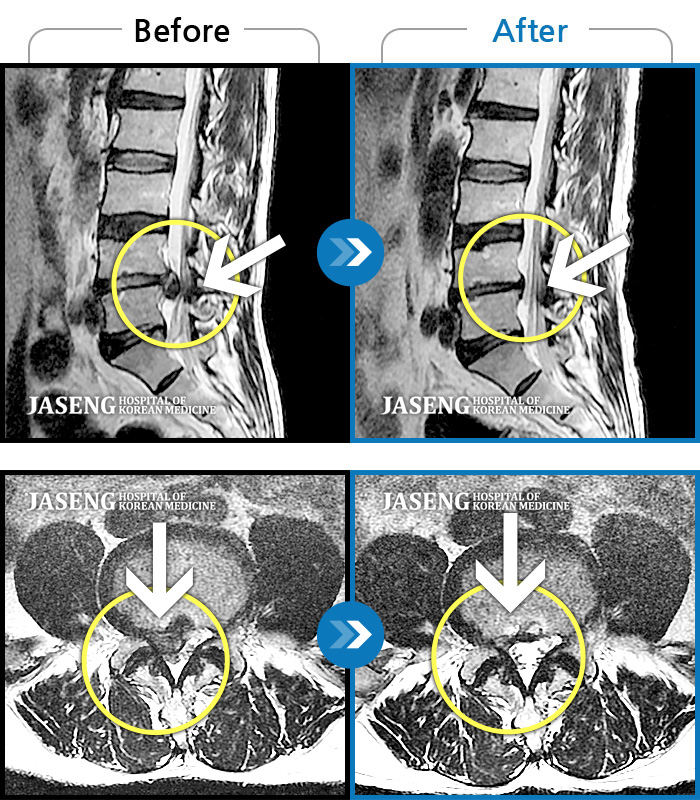

허리디스크

일산 · 김태용 원장

허리와 우측다리가 심하게 저렸다.

촬영시기

2020.05.07 ~ 2020.12.29

2021.02.26